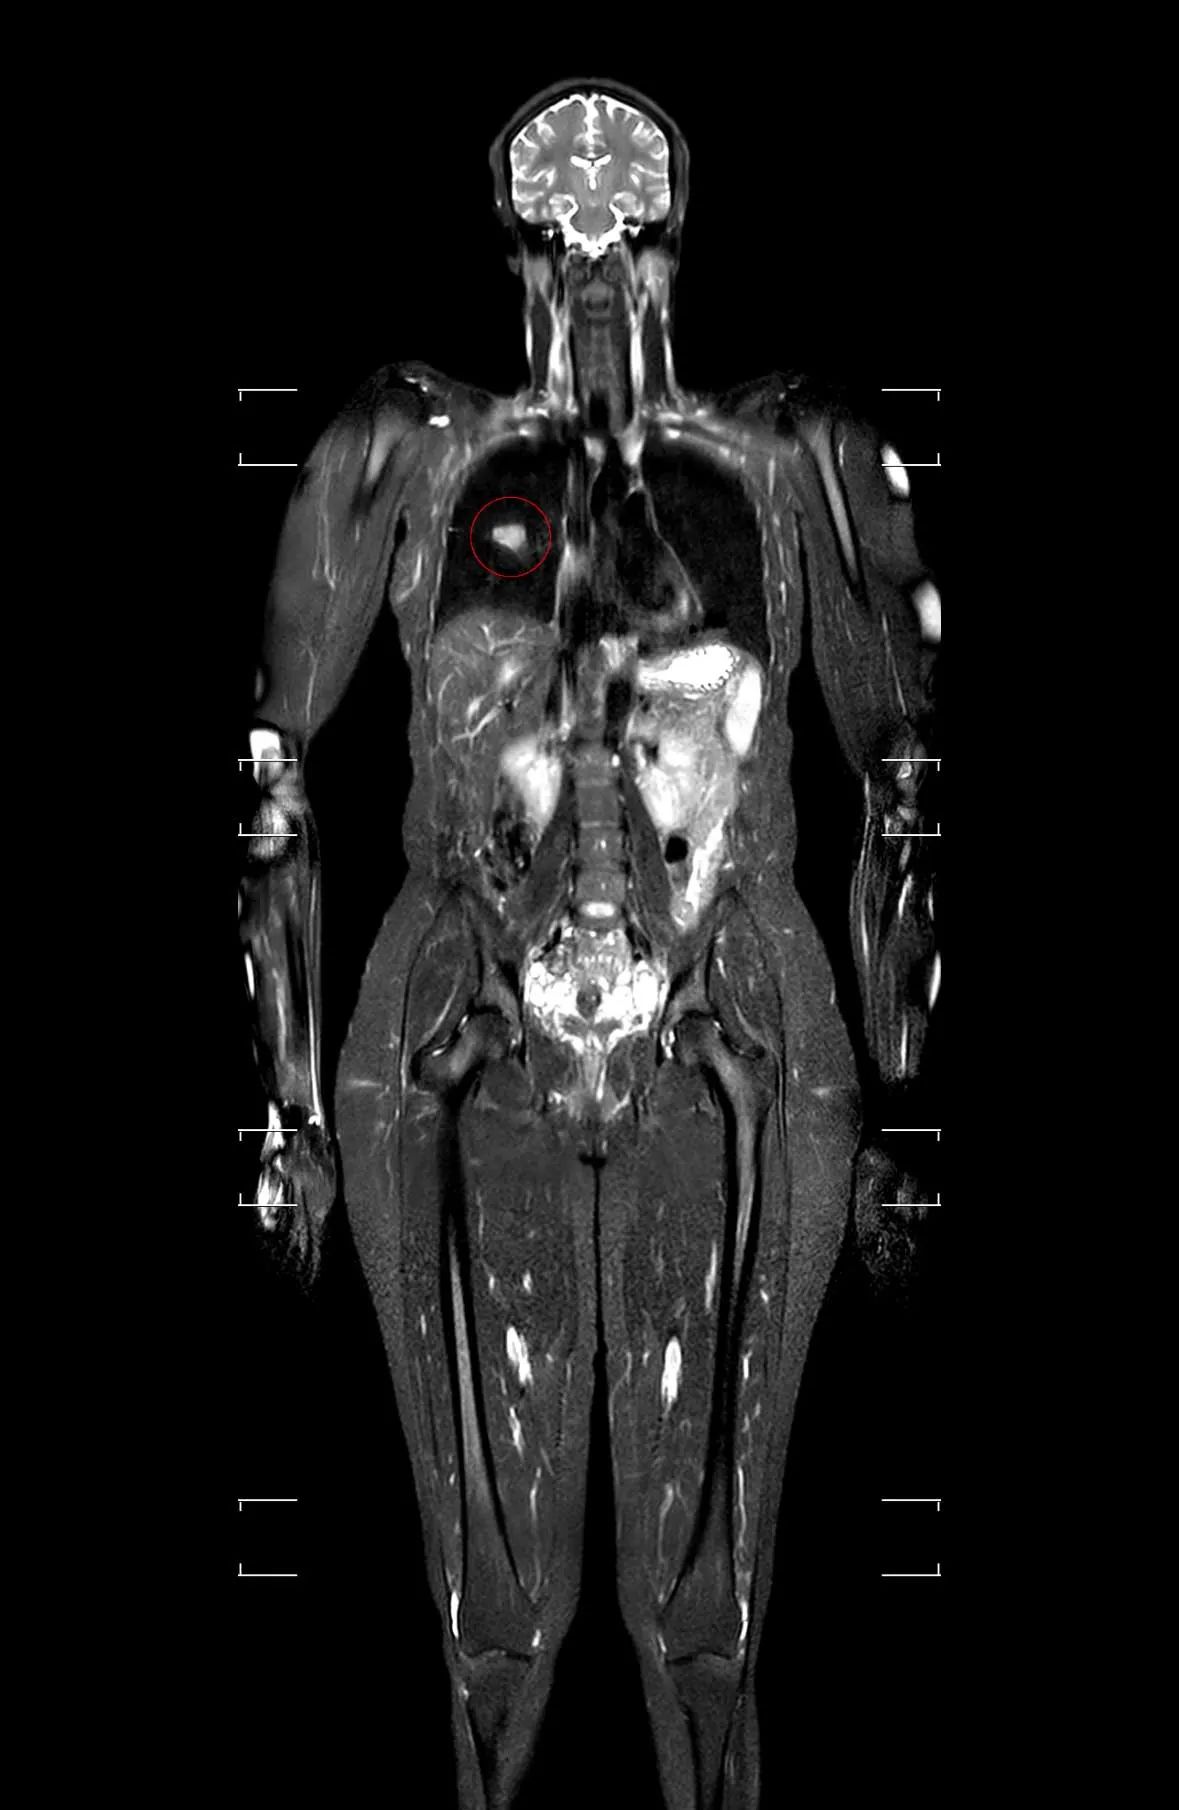

Tuttavia, mentre Jesse è risultato in perfetta salute, la scansione di Dionne ha rivelato una massa sospetta nel polmone destro. “C’è una massa piuttosto grande nel tuo polmone destro e devi chiamare un pneumologo il prima possibile”, le è stato comunicato.

Inizialmente scettico riguardo “questi nuovi macchinari” il pneumologo ha poi prescritto ulteriori esami, che hanno confermato la diagnosi: cancro ai polmoni al terzo stadio. “Se avessi scoperto questo sei mesi dopo, staremmo parlando di come rendere confortevole il resto della tua vita”, le ha detto il medico. Una frase che le ha fatto capire quanto fosse vicina alla morte.

Il dottor Graeme Rosenberg dell’USC Keck Medicine di Los Angeles ha operato Donnie Harmon utilizzando il robot chirurgico Da Vinci. L’intervento ha rivelato che il cancro era più avanzato del previsto, interessando anche un linfonodo. “Siamo stati davvero fortunati ad averla portata rapidamente nel nostro team all’USC in modo che fosse operata rapidamente”, ha spiegato il dottor Rosenberg a People. Ha sottolineato come il cancro ai polmoni sia spesso asintomatico fino a stadi avanzati e che non è una malattia esclusiva dei fumatori, come dimostra il caso di Harmon, che non è una fumatrice.